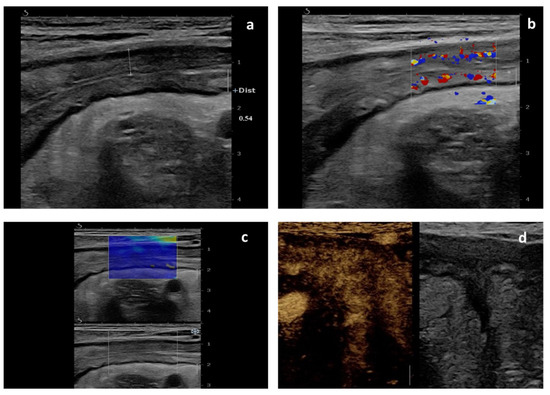

Intestinal Elastography in the Diagnostics of Ulcerative Colitis: A Narrative Review

Ulcerative colitis (UC) is an inflammatory bowel disease (IBD) that mainly affects developed countries, but the number of cases in developing countries is increasing. We conducted a narrative review on the potential application of ultrasound elastography in the diagnosis and monitoring of UC, [...] Read more.

Ulcerative colitis (UC) is an inflammatory bowel disease (IBD) that mainly affects developed countries, but the number of cases in developing countries is increasing. We conducted a narrative review on the potential application of ultrasound elastography in the diagnosis and monitoring of UC, as this newly emerging method has promising results in other gut diseases. This review fulfilled the PRISMA Statement criteria with a time cut-off of June 2022. At the end of the review, of the 1334 identified studies, only five fulfilled all the inclusion criteria. Due to the small number of studies in this field, a reliable assessment of the usefulness of ultrasound elastography is difficult. We can only conclude that the transabdominal elastography examination did not significantly differ from the standard gastrointestinal ultrasonography examination and that measurements of the frontal intestinal wall should be made in the longitudinal section. The reports suggest that it is impossible to estimate the clinical scales used in disease assessment solely on the basis of elastographic measurements. Due to the different inclusion criteria, measurement methodologies, and elastographic techniques used in the analysed studies, a reliable comparative evaluation was impossible. Further work is required to assess the validity of expanding gastrointestinal ultrasonography with elastography in the diagnosis and monitoring of UC. Full article

Show Figures